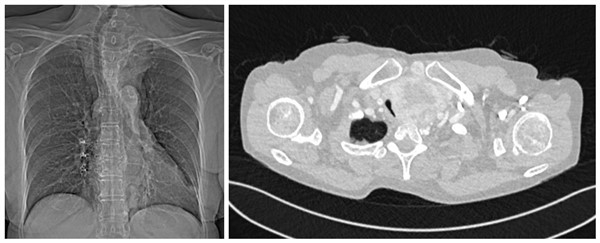

术前胸部CT:颈部及前纵隔肿块巨大,压迫导致气管狭窄并右偏明显